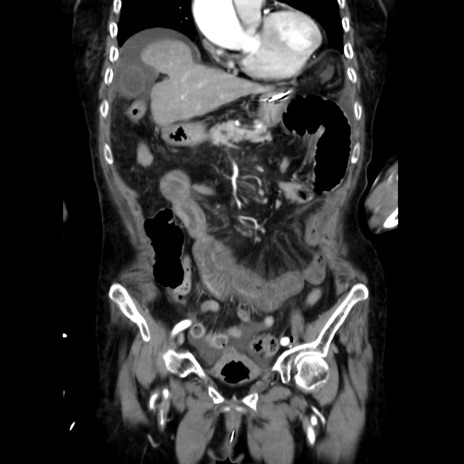

症例40(冠状断像)

【症例】90歳代女性

【主訴】腹痛・嘔吐

【現病歴】 食欲低下、嘔吐があり昨日他院受診。肺炎と診断され入院となる。入院後より腹部全体に圧痛あり。胃管留置され経過みていたが、症状持続するため、

当院転院となる。

【既往歴】胸椎圧迫骨折、胆石症

【身体所見】腹部:中央に激痛あり、圧痛あり、反跳痛不明

【データ】WBC 17100、CRP 18.82

冠状断像